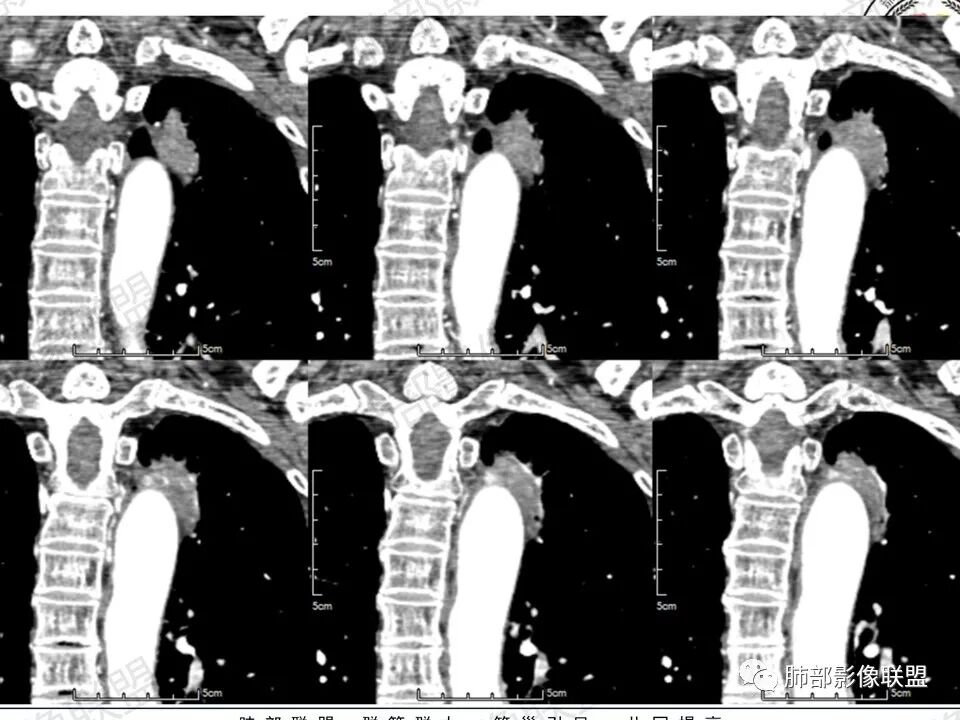

4.冠矢状位病灶于弓上部偏后局限性“贝雷帽”状突起,提示病灶有局部膨隆特点,且病灶上份及后份饰以边缘较清楚磨玻璃影。

2.主动脉弓旁贴合弧形高密度影尤其常见于相应肺组织局限性不张和/或感染。

3.如前所述本例病灶定位于尖后段肺组织,冠矢状位病灶明显局限性膨隆感,如有老师分析时称“见较清楚磨玻璃边缘”——这应当是本例较重要诊断线索!

4.病灶显著强化是符合腺癌影像学特点的。